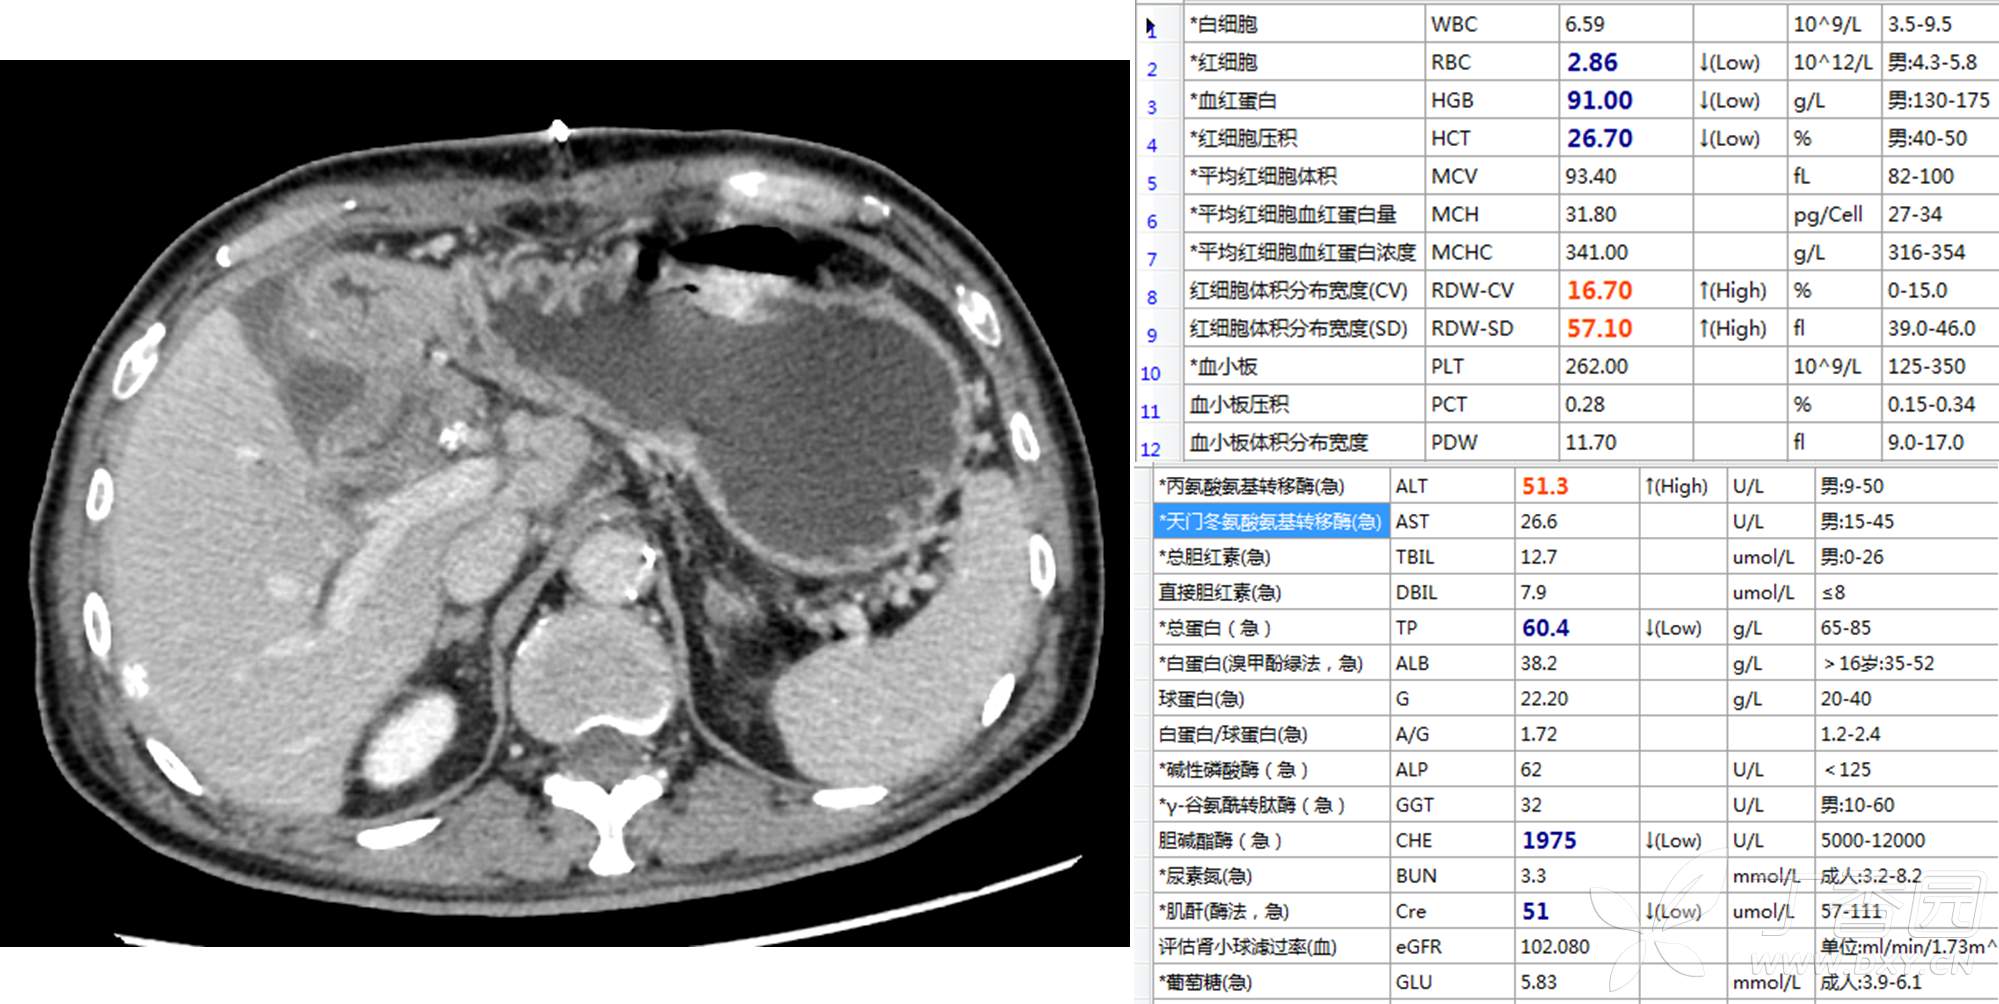

入院后消炎、解痉、补液治疗,患者一般情况明显好转,术前一天的化验单如下:

术前诊断:1、梗阻性黄疸并胆管炎;2、肝内外胆管结石;3、左肝萎缩不除外癌变;4、先天性胆管总管囊状扩张;4、乙肝。